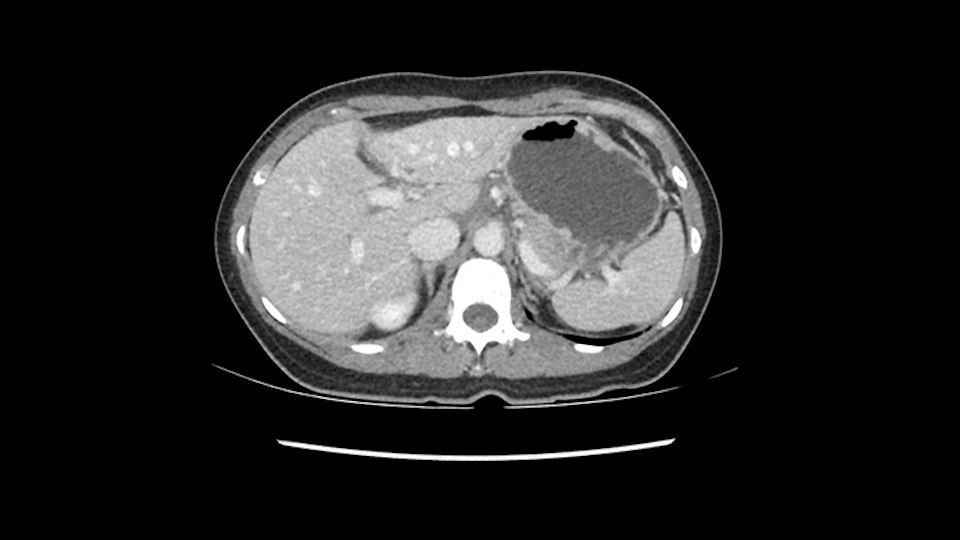

So if we look at the CT scan, on the axial, it’s a larger lesion. It’s about 6 or 7 or 8 centimeters. So it does look a bit threatening in terms of its resectability but if you really drill down deeply into the anatomy, and I think the coronal [imaging] is even better, you can see that the entire mass is on the patient’s left side of the falciform ligament. So it’s really only a left-sided tumor and not even really a left-sided tumor because Segment 4 is uninvolved anatomically.

None of the parenchyma is affected and this tumor is very exophytic; like many Hepatitis B hepatomas; and otherwise is resectable with either a wedge resection part of Segment 2-3 or a formal left lateral segmentectomy.

As I review the CT scan, we have both arterial and venous phases, the tumor is obvious. But I’ll start by saying that the liver itself does not appear to be cirrhotic to my eye. It’s got a normal contour and allied to that, that I do not see evidence of portal hypertension. The spleen is normal, there’s no collateral vessels. The tumor itself, I measured maximally at about 11 centimetres in diameter and I’m told the alpha fetoprotein is very high (over 10000), which is entirely consistent with this being a solitary hepatocellular carcinoma that is very exophytic. It seems to emanate off the inferior margin of Segment 3 (because that’s the falciform). I’ll start by saying that this is not transplantable. The tumor exceeds our guidelines for transplantation, but it's likely resectable based on normal liver and no portal hypertension.

So the issue with regards to resection. A left sided tumor. I believe I can see the falciform ligament right here so we’re looking at a resection of Segments 2, 3 of the left lobe of the liver. The left portal vein is right there. I think we’ll be wiser to take the left portal vein and therefore get well into Segment 4 and do a left hemihepatectomy. Certainly, one does not need to take the middle hepatic vein; it’s miles from the tumor.